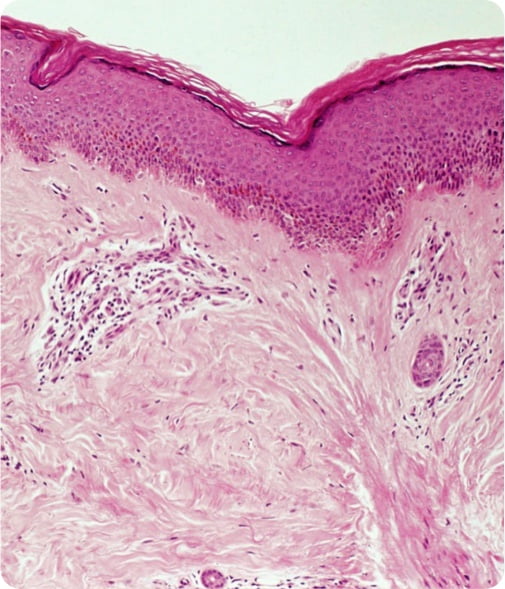

SYSTEMIC SCLEROSIS

What it is

A multisystem autoimmune disease that is characterized by widespread vascular dysfunction and progressive fibrosis (scarring) of the skin and internal organs.

Where it strikes

The prevalence of systemic sclerosis is estimated to span from 50 to 300 cases per 1 million people.5

Current treatments

While some treatments may alleviate symptoms, there are currently no effective or approved therapies for the underlying disease process.